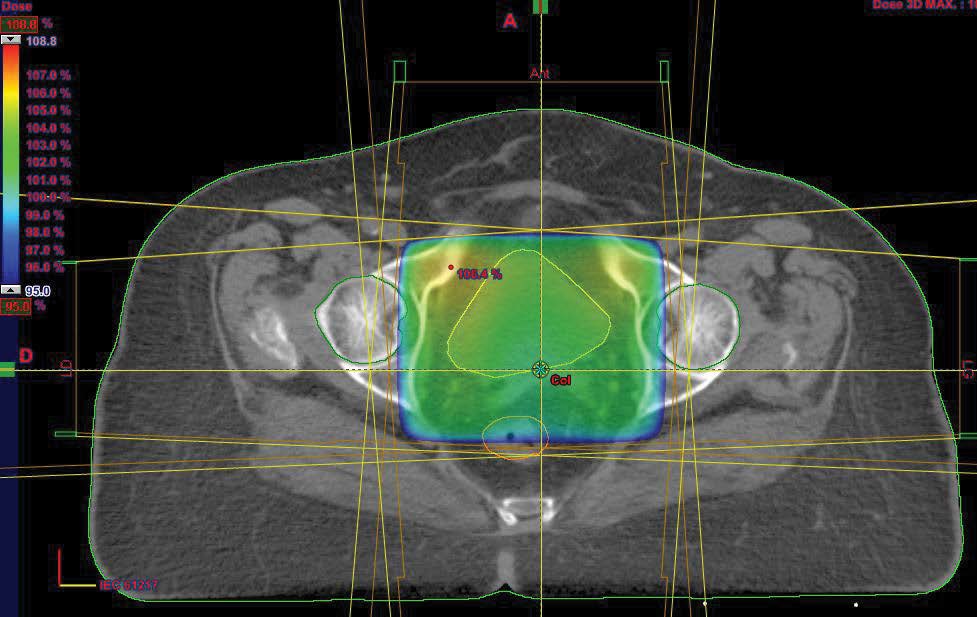

External pelvic radiotherapy was performed at a total dose of 46Gy; 2Gy/Fr in 23 sessions (Figure 2); followed by two 5Gy barrier brachytherapy sessions (Figure 3,4). Three months after the end of the treatment, the clinical examination, the thoraco-abdominopelvic CT scan were normal. During the quarterly controls, the patient is still in good locoregional control and at a distance from the disease.

Figure 2: Axial cut of optimization of dosimetry in external radiotherapy.